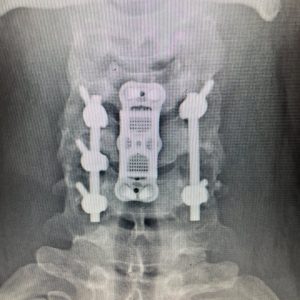

He had a fracture with the instability of his cervical spine at C5, requiring anterior and posterior surgery to decompress the nerve roots and stabilize his unstable cervical spine. He was lucky! His numbness improved, and he made a full recovery.